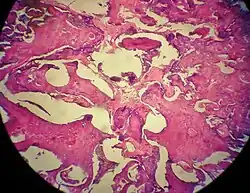

Histopathology

Odontomas are from mixed epithelial and mesenchymal components which are required for tooth development, producing enamel, dentine, cementum and pulp tissue. [6]